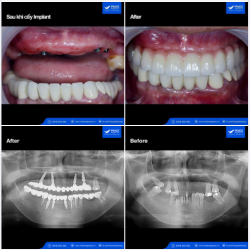

Cấy thêm 2 Implant hàm trên, R16, R26, phục hình sau 2 tháng.

Ca lâm sàng ???-??-? ??????? (??) ???̣? ??̀?? ??̛́? ???̀ ??̛́? ??̀? ??????, kết hợp cấy 2 Implant (HT) (???????: ????????? ??? ???, ???? ?? ???????????) ...

Ca lâm sàng: ???-??-? ??????? (??) + ? ??????? ??̀ ??̂̀? ??̆?? ??̛́ (??) → VẤN ĐỀ CHÍNH YẾU: Khách hàng đến Peace Dentistry với tình trạng: ✓ Hàm trên:...